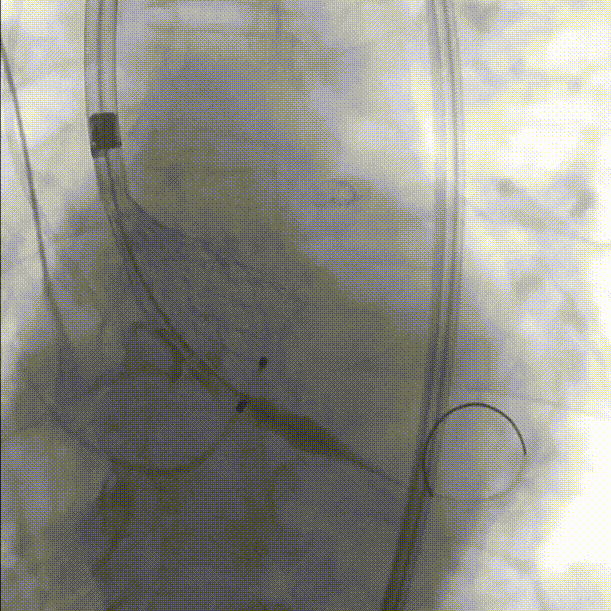

术后导管测压压差为2mmHg:

最终根部造影:无反流,冠脉灌注良好:

超声复查,支架形态满意,手术结束:

美敦力Evolut PRO植入术后,最终根部造影,未见反流,冠脉灌注良好,手术结束。